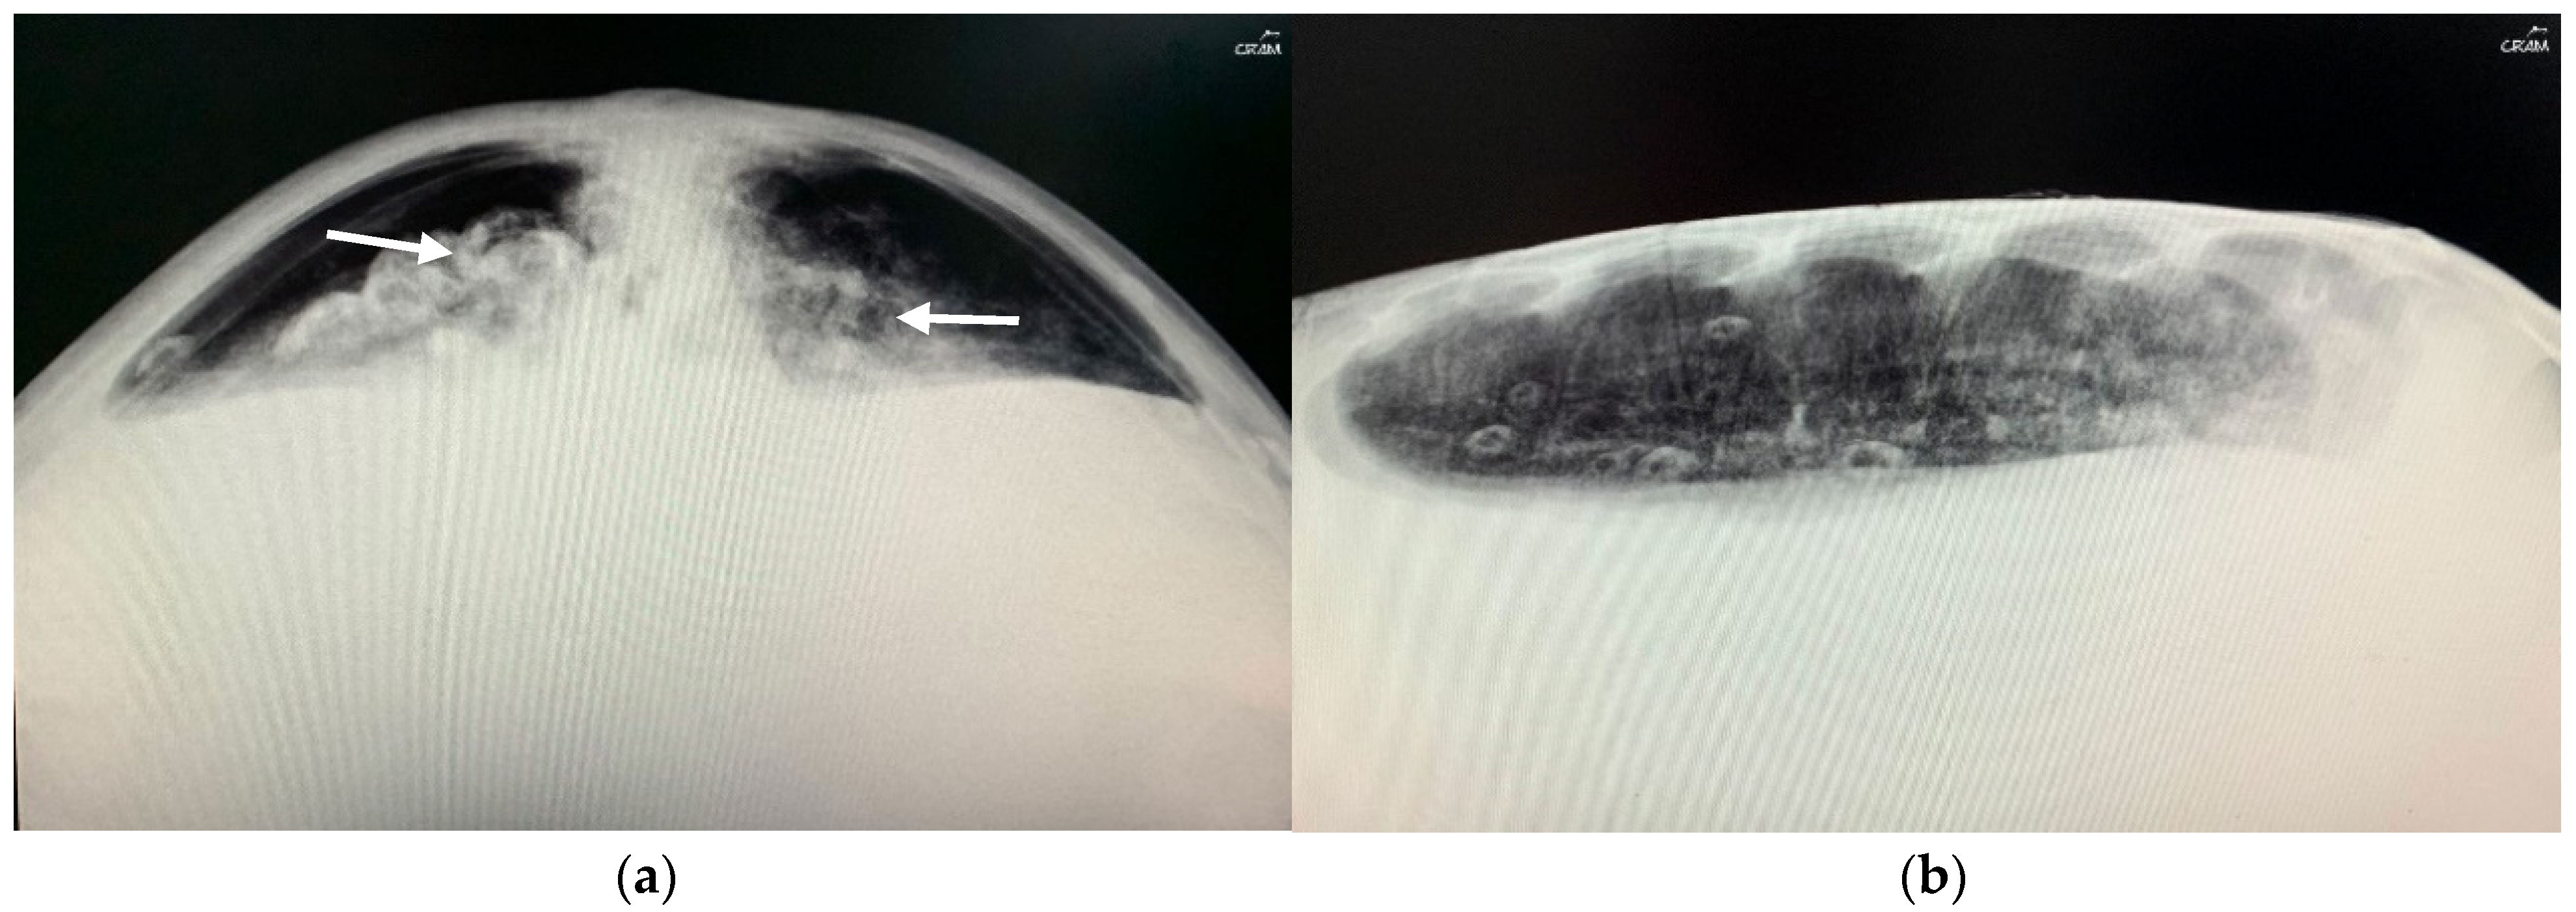

In December 2020, CC20/051 suffered a bycatch incident by a trawler ship. At the rescue center, it was diagnosed with pneumonia by radiography (Figure 3) and started treatment with ceftazidime 22 mg kg−1, SC q 72 h for 15 days. In January 2021, the turtle was released.

Figure 3.

Radiographic examinations in cranio-caudal (a) and lateral (b) projections of the lungs. The images show an opacification of the whole parenchyma following bacterial pneumonia. The arrows show a densification of the peribronchial lung parenchyma.